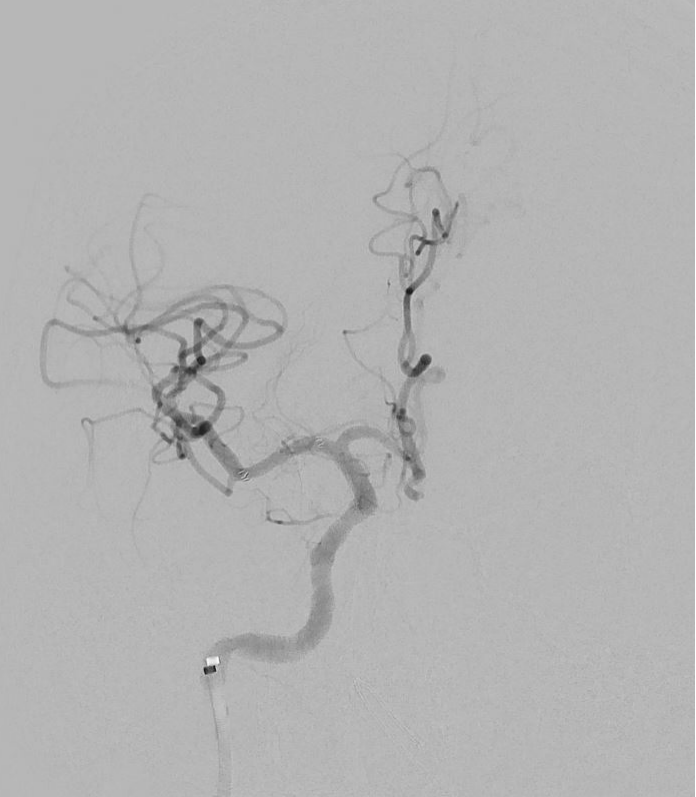

术后DSA:右侧大脑中动脉未见明显残余狭窄,远端分支未见残端

术后PWI:右侧岛叶、颞叶、右侧脑室旁及放射冠区血流明显改善